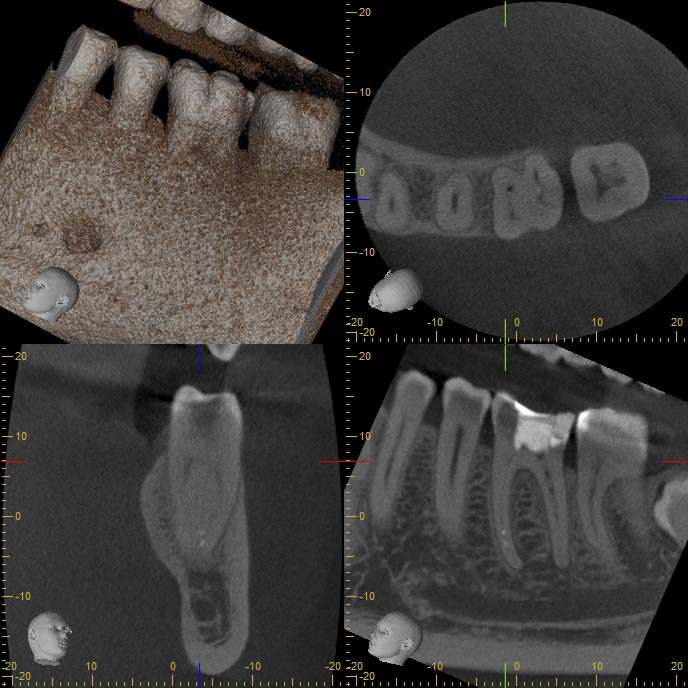

BF36-1 Veröffentlicht 24. Februar 2014 am 688 × 688 in Wann ist ein DVT sinnvoll ? – Fortsetzung Beitrag 13.12.2013